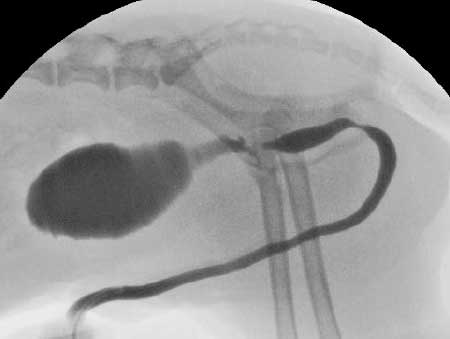

造影方法は静脈性と逆行性の2種類があります。静脈性尿路造影は、静脈から造影剤を投与して造影剤の尿中への排泄を経時的に確認する方法で、腎臓や尿管の構造の評価や尿生成過程から腎機能の評価を行うことが可能です。逆行性尿路造影は、ペニスや膣など陰部から造影剤を投与する方法で、奇形や腫瘤といった形態上の異常や膀胱から尿道にかけての尿路の狭窄や断裂・破裂の有無を評価することが可能です。

静脈性尿路造影/ 右腎の排泄性低下を認める

当院ではCアーム(X線撮影装置)を使用することにより、尿排泄の様子や造影剤の流れなど動的な評価も可能です。

逆行性尿路造影/ 前立腺尿道の狭窄を認める